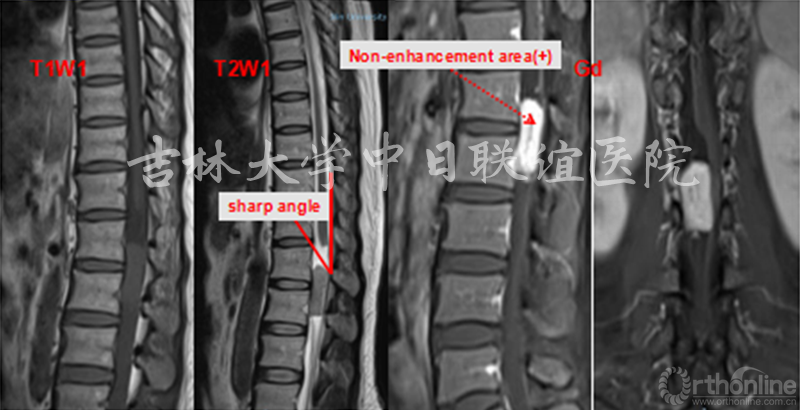

MRI:T1W1:相对脊髓呈等信号;T2W1:相对脊髓呈略高信号,瘤体与硬膜呈锐角,脑脊液在瘤体上缘增宽呈“杯口征”(瘤体位于硬膜下);MRI Gd:肿瘤边缘明显强化,瘤体中央伴有不均匀性增强。肿瘤与脊髓之间呈锐角,形成“肩胛征”,脊髓呈鸟嘴样改变(髓外)。

X线平片和CT检查均需要依据钙化或肿瘤引起的明显骨质改变而检出病灶,阳性率较低,但是有助于了解脊柱的稳定程度、对手术方案的制定提供帮助;脊髓造影为有创性检查,通过肿瘤与造影剂的作用(如表现为充盈缺损等)对肿瘤的定位诊断有一定的帮助,但是对于肿瘤定性存在困难。MRI对椎管内软组织分辨率高并且能够避免骨骼的伪影,根据不同肿瘤相对特征性的MRI表现可以获得较为准确可靠的定位及定性诊断,有利于术前制定合理的手术方案。

神经鞘瘤(Neurinoma)

我们回顾性分析了我院108例(111个病灶)硬膜下髓外肿瘤病例特点;神经鞘瘤69(70病灶),脊膜瘤31(31病灶),神经纤维瘤3(5病灶),畸胎瘤4(4病灶),转移性肿瘤1(1病灶)。不同肿瘤的MRI表现具有一定的特异性:

3.MRI上总结出的一些特点可以帮助术前预判;